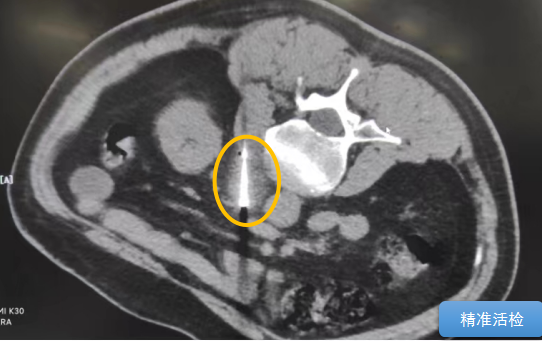

經(jīng)過多學(xué)科討論,陳寶瑩主任根據(jù)影像資料指出,患者轉(zhuǎn)移瘤位于腹膜后,內(nèi)側(cè)瀕臨人體最大的血管——主動脈;前方同樣有血管緊貼腫瘤;外側(cè)是腎臟,后方是椎體和神經(jīng),夾縫中進(jìn)針難度大,治療時要避免周圍重要臟器、血管和神經(jīng)的損傷,因此可以選擇CT引導(dǎo)下精準(zhǔn)穿刺活檢同步冷凍消融治療,即獲得病理組織有利于下一步全身治療方案的調(diào)整,同時殺死腹膜后轉(zhuǎn)移瘤,周圍正常組織損傷的可能性也小。

術(shù)中陳寶瑩主任、李鐵柱教授、兀云飛醫(yī)生、魏東紅技師、汝平護(hù)士協(xié)調(diào)配合,夾縫進(jìn)針難度雖大,但在CT引導(dǎo)下逐步進(jìn)針,精準(zhǔn)到位,順利活檢取得組織,由于腫瘤較大,為了提高消融效率,平行置入兩根冷凍消融針,同時啟動冷凍消融,術(shù)中清晰觀察到冰球完全覆蓋病變,患者沒有任何不舒服,治療中還可以和醫(yī)生聊天。